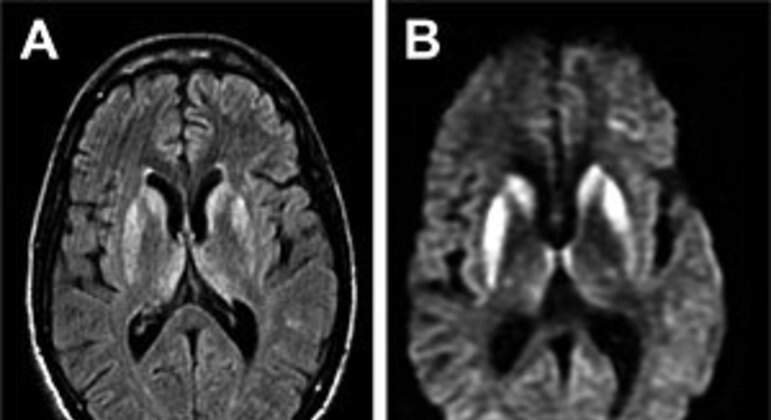

Doença é rara e ataca o sistema nervoso central. (Foto: Reprodução)

Horas após confirmar que dois pacientes estavam internados no Rio de Janeiro com suspeita de EEB (encefalopatia espongiforme bovina), conhecida popularmente como “doença da vaca louca”, o INI/Fiocruz (Instituto Nacional de Infectologia Evandro Chagas/Fundação Oswaldo Cruz) descartou a hipótese de que os casos tenham relação com o consumo de carne contaminada.

Em nota, o vice-diretor de serviços clínicos da instituição, Estevão Portela Nunes, afirma que, “considerando os aspectos clínicos e radiológicos”, os casos estão sendo tratados como “suspeita da forma esporádica da doença de Creutzfeldt-Jakob”.

De acordo com o Manual MSD de Diagnóstico e Tratamento, a DCJ (doença de Creutzfeldt-Jakob) também é uma encefalopatia espongiforme, mas mais comum do que a doença da vaca louca.

A forma esporádica é, segundo o guia, o tipo mais comum, representando 85% de todos os casos. “A DCJ esporádica geralmente afeta pessoas com mais de 40 anos de idade (média etária de cerca de 65 anos).” A doença da vaca louca é classificada como a forma adquirida.

As duas são doenças neurodegenerativas raras e denominadas priônicas, por serem causadas por príons – formas modificadas de uma proteína presente normalmente no organismo.

Os sintomas incluem demência, mioclonia (espasmos e contrações musculares) e outros déficits no sistema nervoso central. A morte geralmente ocorre entre quatro meses e dois anos após a infecção, a depender da modalidade e do subtipo da DCJ. O tratamento é apenas de suporte.